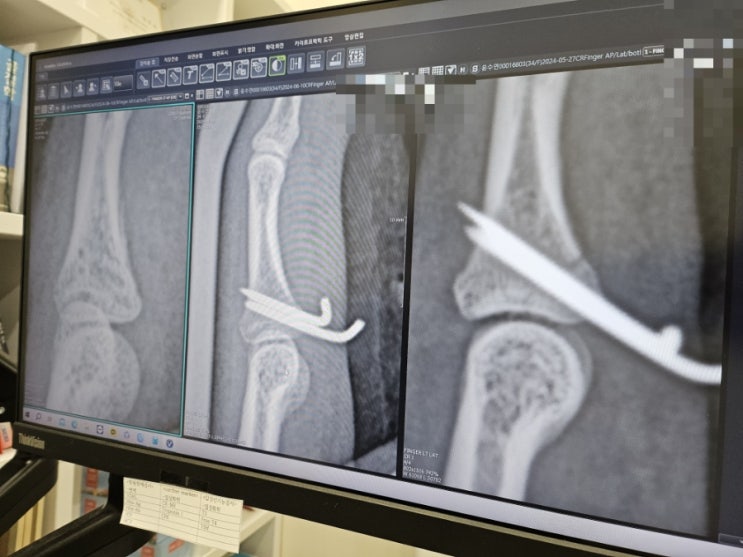

손가락 골절 수술 후 재활 후기

2024. 5. 2 왼손 검지 손가락 골절 5.3 손가락 골절 수술 핀 두개 박음 6.10 손가락 골절 수술 때 박은 핀 ...

손가락 골절 수술 핀 제거 후기

2024.5.2 저녁 7시경 배구하다가 오버로 공격공 캐치하다가 왼쪽 검지 손가락 골절. 이래서 잘한다. 좀 하...